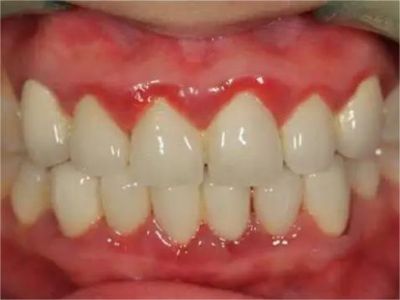

急性坏死性溃疡性龈炎起病急,病程短,常为数天至1-2周,以龈乳头和龈缘的坏死为其特征性损害,尤以下前牙多见,初起时龈乳头充血水肿,个别龈乳头顶端可发生坏死性溃疡,上覆有灰白色坏死物,中央凹下如火山口状。龈缘如虫蚀状,坏死区出现灰褐色假膜,擦去后可见出血创面。龈乳头被破坏后与龈缘成一直线,如刀切状。病损一般不波及附着龈,患处牙龈极易出血,疼痛明显并有腐败性口臭。